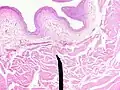

Microanatomy

When viewed under a microscope the bladder can be seen to have an inner lining (called epithelium), three layers of muscle fibres, and an outer adventitia.[6]

The inner wall of the bladder is called urothelium, a type of transitional epithelium formed by three to six layers of cells; the cells may become more cuboidal or flatter depending on whether the bladder is empty or full.[6] Additionally, these are lined with a mucous membrane consisting of a surface glycocalyx that protects the cells beneath it from urine.[12] The epithelium lies on a thin basement membrane, and a lamina propria.[6] The mucosal lining also offers a urothelial barrier against the passing of infections.[13]

These layers are surrounded by three layers of muscle fibres arranged as an inner layer of fibres orientated longitudinally, a middle layer of circular fibres, and an outermost layer of longitudinal fibres; these form the detrusor muscle, which can be seen with the naked eye.[6]

The outside of the bladder is protected by a serous membrane called adventitia.[6][14]

Vertical section of bladder wall

Layers of the bladder wall and cross-section of the detrusor muscle

Anatomy of the male bladder, showing transitional epithelium and part of the wall in a histological cut-out